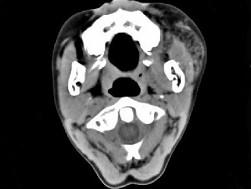

问题 男,12岁,左面颊肿大5年余,局部呈紫红色,CT如图所示,最可能诊断为 ( )

选项 A、慢性腮腺炎 B、下颌下腺慢性炎症 C、血管外皮瘤 D、动静脉畸形 E、蔓状血管瘤

答案 E